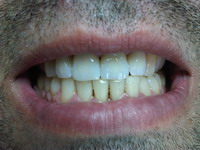

Obturatii nefizionomice pe

dintii frontali